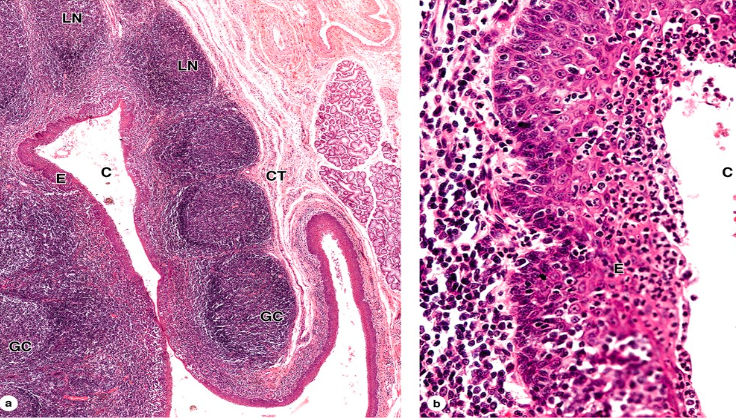

What is this? label

Tonsil. Lymphatic nodules covered by stratified squamous epithelium

some nodules show light staining germinal centers (GC). Infoldings of nodules form CRYPTS (C)

E= epithelium SS